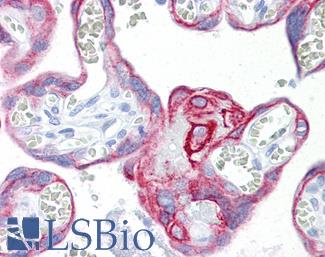

CK7 (KRT7)

Anti-KRT7 / Cytokeratin 7 antibody IHC of human placenta. Immunohistochemistry of formalin-fixed, paraffin-embedded tissue after heat-induced antigen retrieval. Antibody LS-B7163 concentration 10 ug/ml.